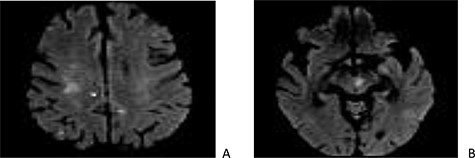

The cerebral magnetic resonance imaging (MRI) revealed a sequelae ischemic strokes with lesions of different ages in the territory of both the left sylvic artery and branches of the basilar artery (cortical, subcortical and mesencephalic) (Fig. 1).

Cerebral magnetic resonance imaging (MRI): sections in diffusion at 1000 b showing punctiform cortico-subcortical (A) and mesencephalic (B) lesions related to embolic infarcts.